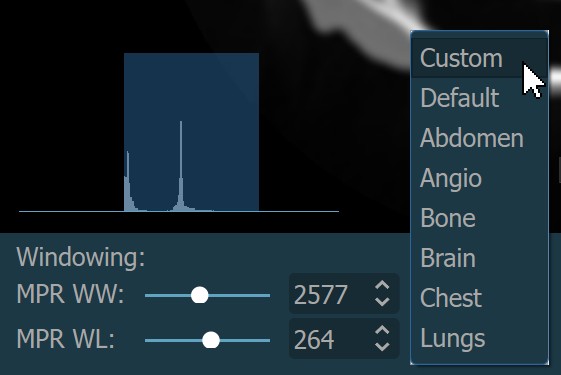

Users can manually change the windowing settings by dragging the MPR WW and MPR WL sliders to the desired direction, or use the subsequent input fields to enter the specific values directly from the windowing section when the default

mode is active.

Additionally, choose one of the available windowing presets from the dropdown to directly apply the corresponding window center and window width values.

Histogram¶

A windowing histogram is a graphical representation of the distribution of intensity values in an image. It displays the number of pixels at each intensity level, allowing users to adjust the brightness and contrast by setting a window around a range of intensity levels. By adjusting the position and width of the window, the user can optimize the image for their specific needs and better visualize the image features.

To change the window width, press and drag the left or right edge of the rectangular area representing the window.

To change the position or the window center, press and hold on the rectangular area and drag in the desired direction.